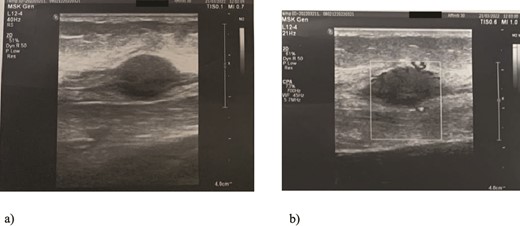

We present a case of a 49-year-old, female patient who presented at our clinic complaining of a growing painful mass with a diameter of ⁓3 cm in her left calf. The patient noticed the mass 2 months before the clinical exam and according to the anamnestic data it was growing progressively, becoming more painful, but only when touched, not spontaneously. She was first seen in another clinic, an ultrasound was performed and excision in local anesthesia was suggested. On presentation, clinical and ultrasound examinations were performed. Clinical exam revealed presence of a soft tissue mass on the medial side between the proximal and medial third of the left calf, of ⁓3 cm. It was placed deep in the subdermal area, mobile and not connected to the fascia. The ultrasound showed a heterogeneous, but predominantly hypoechoic mass with increased through transmission and increased vascularization (Fig. 1). Magnetic resonance imaging (MRI) was performed, confirming the presence of a soft tissue tumor in the subcutaneous tissue of the left calf (Fig. 2). Wide resection of the mass under spinal anesthesia was scheduled. Macroscopy of the specimen showed a whiteish soft fragment measuring 2 × 2 × 0.8 cm, microscopically composed of fibroblastic stroma with myxoid degeneration and immature osteoid embedded in between atypical osteoblasts with inconspicuous mitotic activity (Fig. 3). Foci of chondroid matrix with atypical chondrocytes were present. Necrotic and calcified bony trabeculae with osteoblastic rimming and adipose tissue with skeletal muscle were present on the periphery. The proliferative index, Ki67 was ⁓5%, thereupon a diagnosis of low-grade ESOS was made (Fig. 4). The regular staging follow-up was performed with chest and abdominal computed tomography (CT). No signs of metastatic disease were detected. The bone scan with Tc99m showed an increased uptake on the left iliac bone, highly suspected of Paget disease. Another surgery was scheduled. This time, re-resection procedure to achieve negative margins, as well as a biopsy of the iliac wing was performed. Negative margins were accomplished with the re-resection procedure. Grossly, the iliac bone biopsy was composed of five bony fragments measuring 0.5–1.5 cm. Microscopy showed sclerotic and irregularly shaped anastomosing, lamellar bony trabeculae with focal irregular calcification. The trabeculae contain osteocytes without atypia, rimmed with reactive osteoblasts, as well as multinucleated osteoclast giant cells. Granulation tissue with focal collagen deposition was present focally in between the bone trabeculae. Focal bone marrow was present. The microscopic analysis was consistent with the late (sclerotic) phase of Paget disease of bone (Fig. 5). On the last follow-up exam, 2 years after the surgery there is no evidence of local recurrence.

Ultrasound examination of the tumor: Spindle-shaped hypoechogenic and subcutaneously placed mass (a) with marked hypervascularity on color flow mapping (b).